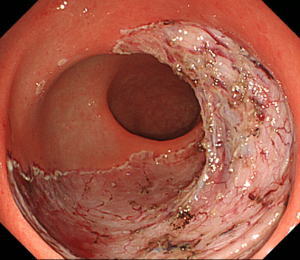

| 【大腸ESD】 |

合併症を生じることなく、粘膜下層剥離が終了しました。 |

最大径90mm近い大きな早期癌でしたが治癒切除されていました。患者さんも合併症を生じることなく、治療の5日後に退院されました。 |